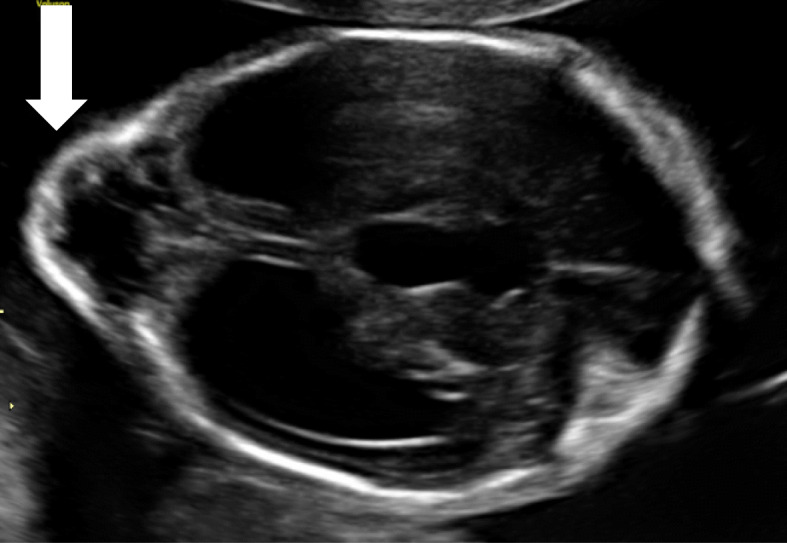

Fig. 2.

Prenatal ultrasound of the brain (22th week of pregnancy): occipital encephalocele (white arrow) and hydrocephalus